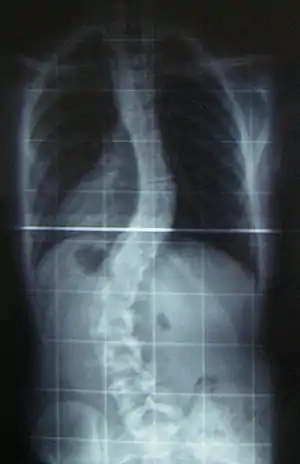

The prognosis of this sub-type of MD indicates that the affected individual may eventually have feeding difficulties. Surgery, at some point, might be an option for scoliosis.[3]

Scoliosis, which is a sideways curve of the persons vertebrate, is determined by a variety of factors, including the degree (mild or severe), in which case if possible a brace might be used by the individual.[14]